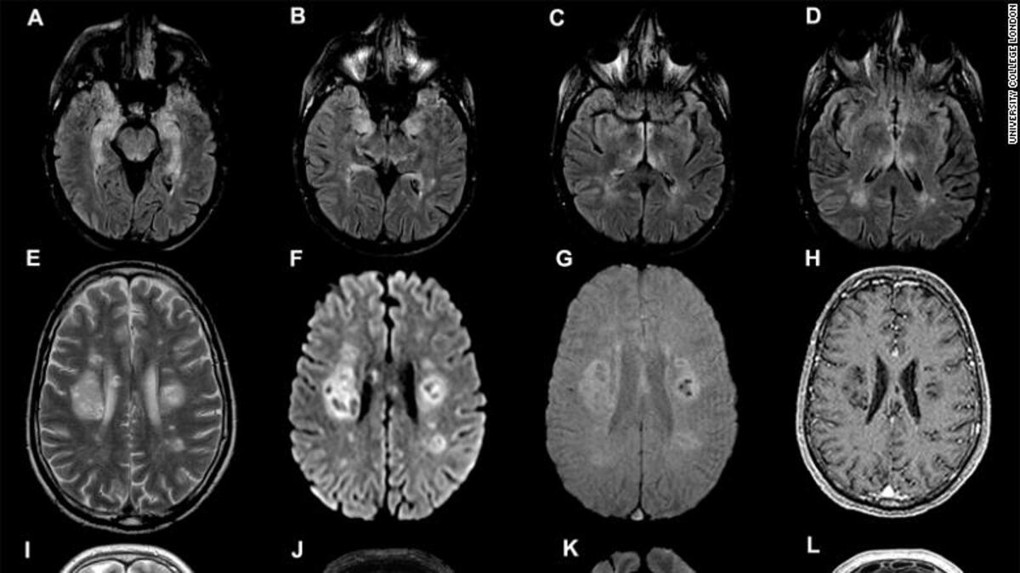

Phổi bệnh nhân phi công Anh 'đông đặc'

Y tế 24h - 18/04/2020

Phổi "bệnh nhân 91" vẫn còn tổn thương nặng chưa cải thiện, tiếp tục "thở" bằng ECMO.